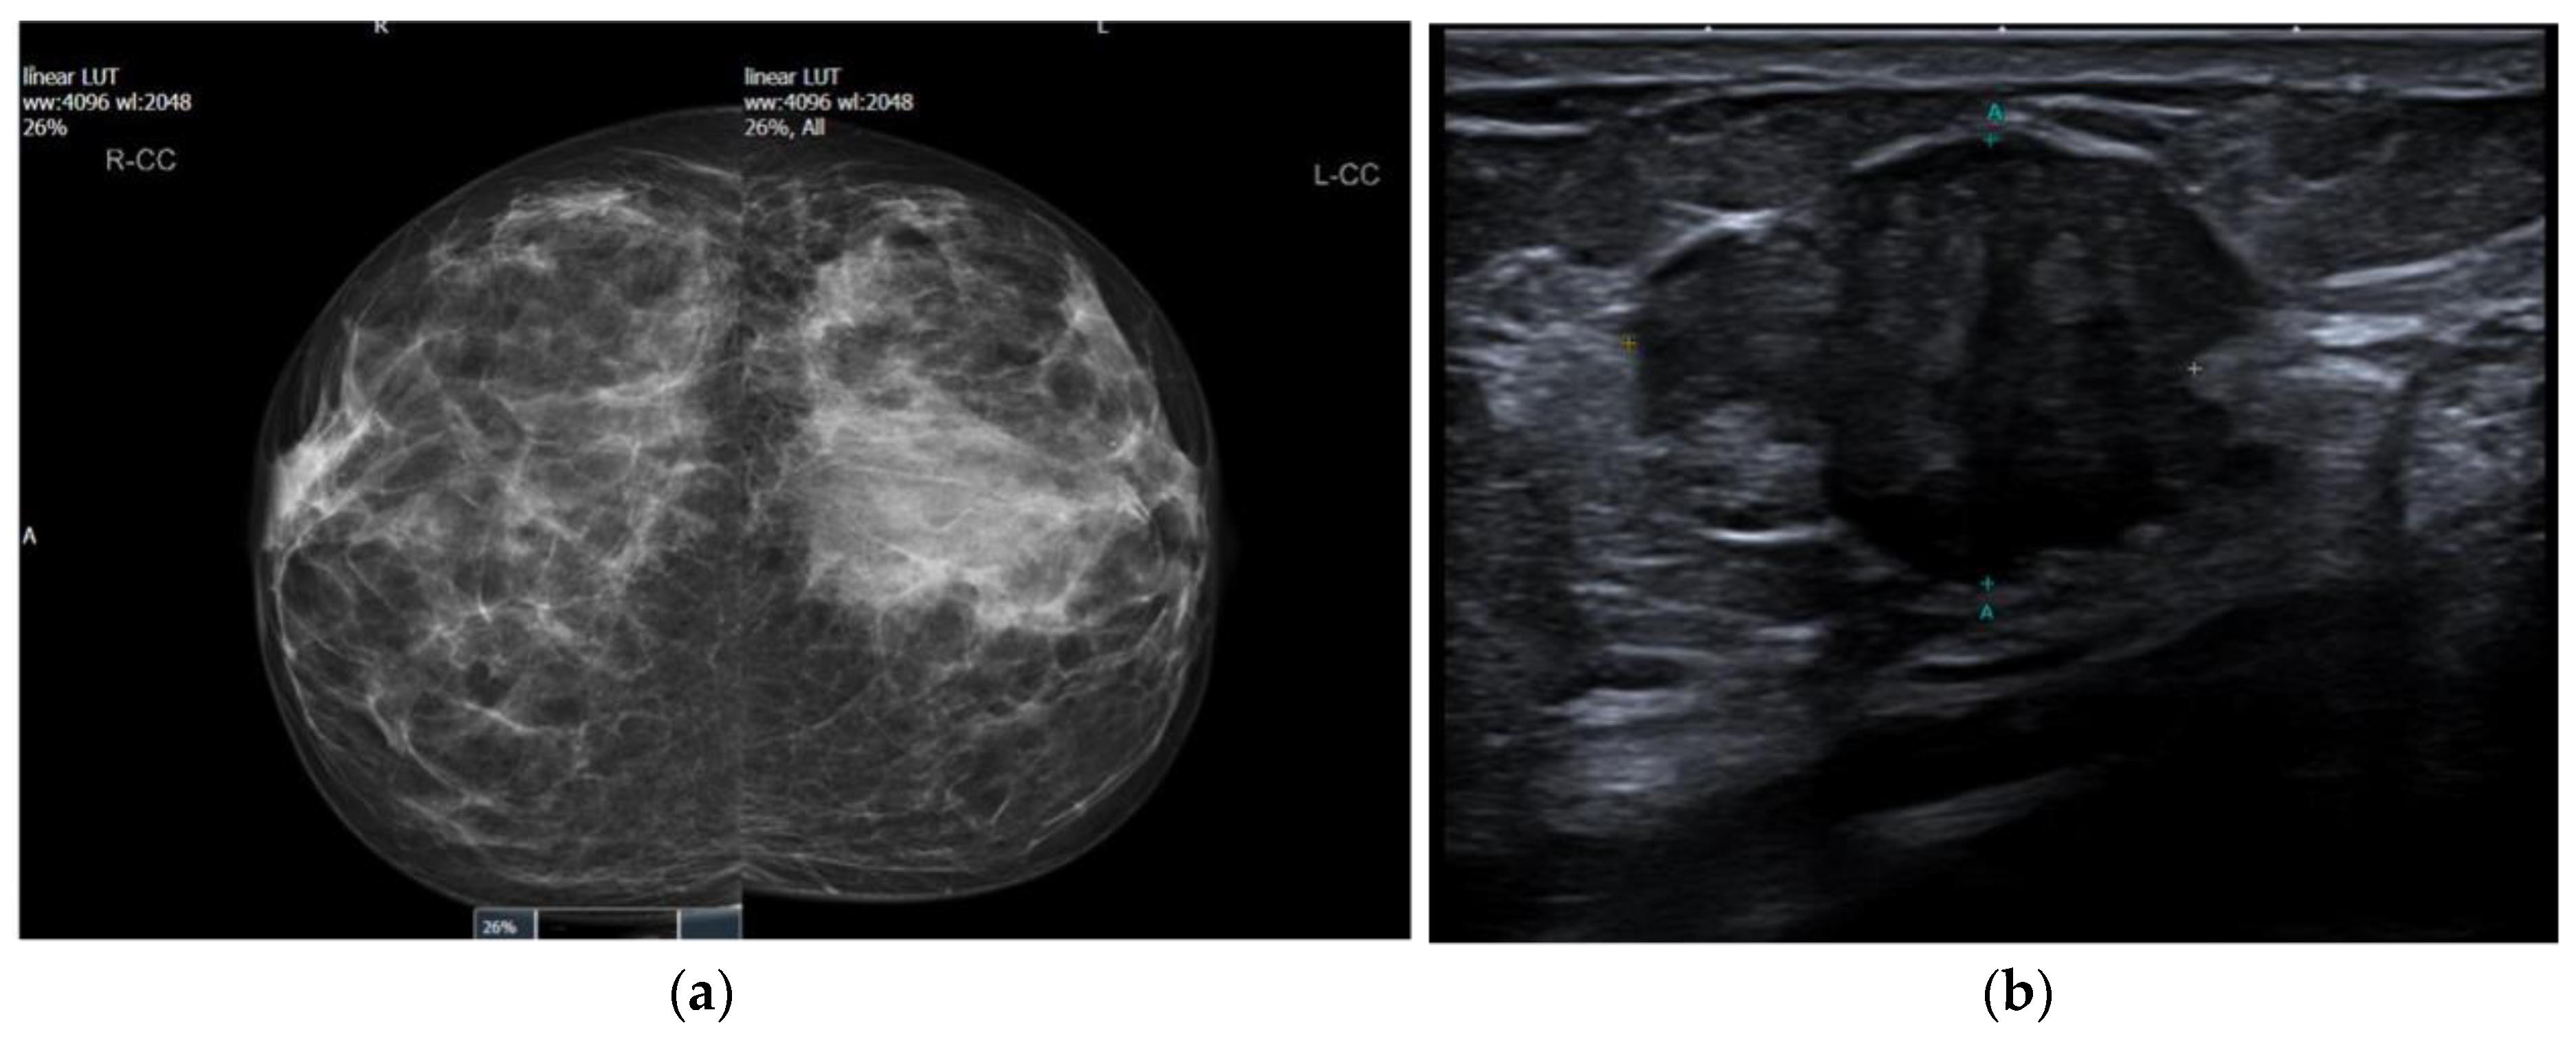

| Elghobashy et al. (current study) | 2023 | 41 | Symptomatic lump | Ill-defined mass with normal axillary nodes | Proliferation of large, tall cells that exhibited solid nests with central fibrovascular cores and associated luminal histiocytes | +ve: CK5, CK7, GATA-3, calretinin −ve: ER, PR, HER2, TTF1, p63 |